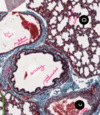

histology resp sys

histology bronchovascular bundle